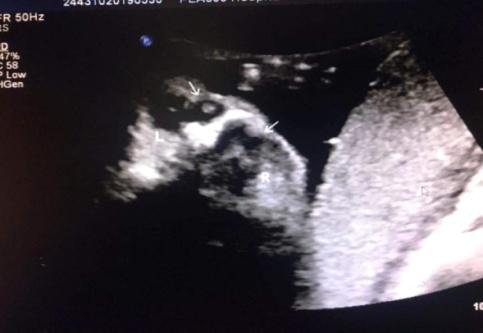

典型案例:孕妇,37岁,孕32周常规产检,系统检查胎儿及附属物,发现胎儿双侧眼眶内下方均可见一无回声区,大小分别约:右侧0.4x0.3cm、左侧0.8x0.7cm,边界清晰,内壁光滑,内透声好,左侧无回声内可见斑块状高回声,彩色多普勒检查其内未见血流信号,余未见异常;孕34周及36周随访复查,双侧无回声区消失。

如此奇妙的现象,到底是怎么回事?根据超声表现特征,考虑此无回声为胎儿鼻泪管囊肿,动态观察更强化了诊断信心。

超声动态观察,能在孕期显示并诊断胎儿鼻泪管囊肿,动态监测其转归,减少孕妇的焦虑,避免不必要的引产。